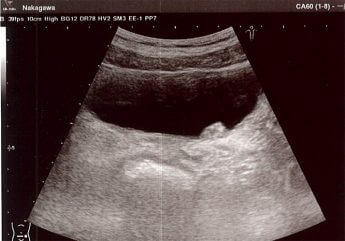

がん週刊新潮 2019年1月31日号掲載

膀胱がんは小倉智昭氏や菅原文太氏も罹ったことで知られている